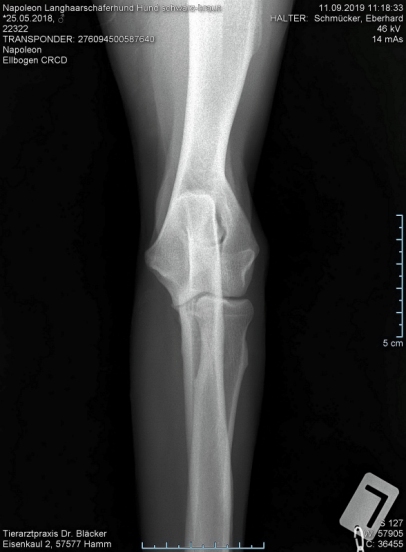

Keine HD  und  kein ED

Röntgentermin am 11.09.2019

Hier sind  HD-ED Aufnahmen von unseren “Napoleon von KaTum”   alles Top

Keine HD und kein ED,LÜW ist alles gut